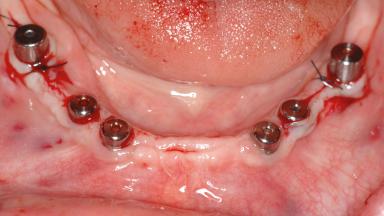

# of Implants 14

Bone Augmentation Horizontal|Sinus Floor Elevation|Staged|Vertical

Augmentation Materials Autogenous chips|Autogenous block(s)|Xenogenous|Membrane

Bone Volume Deficient vertically or deficient vertically AND horizontally